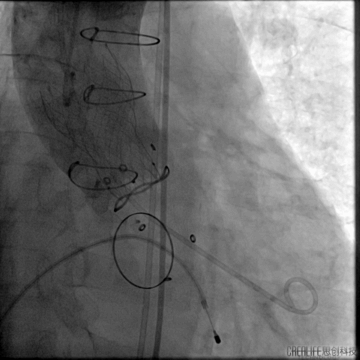

建立瓣周漏轨道

血管塞封堵

12mm三支血管塞置入

术中食道超声确认满意后释放血管塞

跨瓣建立轨道

主动脉瓣架植入

根据造影情况决定选择VenusA 23号瓣膜

主动脉瓣架释放